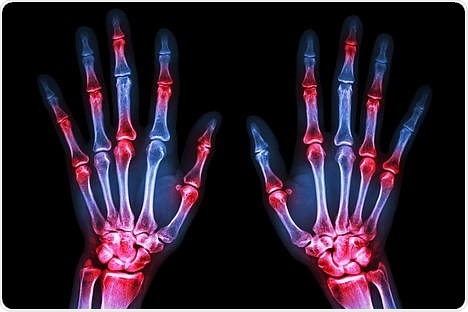

Rheumatoid arthritis is a common inflammatory joint disease. A feature of this disease is the increased fusion of endogenous immune cells (macrophages) to form so-called osteoclasts, which attack and break down bone tissue.